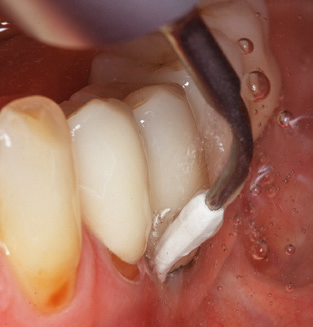

Good illumination of the working field facilitates the process considerably. The system used by the authors achieves this thanks to a 5x LED ring integrated in the handpiece. Naturally, a range of working tips for different indications is also offered. A straight, universally employable tip is the basic instrument required for machine cleaning of natural teeth (Fig. 5a and b). Curved tips, which allow access to exposed furcations, are also available for hard-to-reach areas in the posterior region (Fig. 6).

Of course, working tips for the cleaning of implant surfaces are also indispensable for SPT in patients fitted with implants. The implant cleaning attachment on the system used here is characterised by its tapered, hexagonal design. This design allows light, atraumatic penetration of the peri-implant pocket and displays a good cleaning performance (Fig. 7).